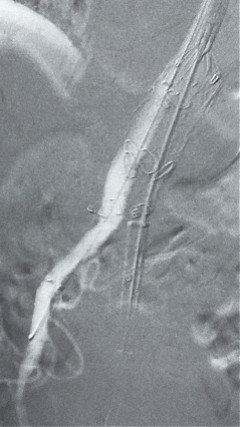

8. 从右侧股动脉入路送入腹主支架AB-24-12-110-S,近端重叠胸腹主动脉支架远端,调整好支架位置后释放。

9. 经左股动脉送入导丝导管,超选进腹主动脉支架短腿内,后沿导丝送入髂支,同理,右侧沿导丝送入髂支并释放,使用J9集团国际顺应性球囊后扩各支架连接处及支架近远端,最后通过预留导管向瘤腔注入人纤维蛋白粘合剂数支,造影显示分支通畅。

术后评价

G-Branch在本例手术中展现出对扭曲解剖结构的出色适应性,针对该患者严重扭曲的瘤颈,支架系统的优异柔顺性使其能够顺利通过复杂路径,完成内脏分支血管的重建。

其独特的双内嵌、双外翻混合多分支设计兼顾了操作效率与结构可靠性,预置导丝系统简化了肠系膜上动脉(SMA)和腹腔干动脉(CA)的超选流程,显著提高手术效率。